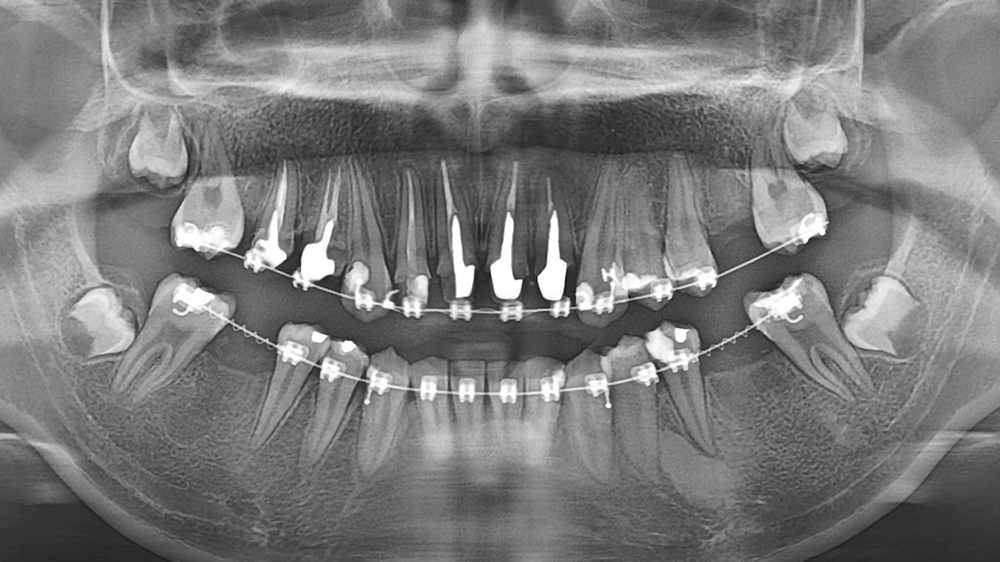

牙齒不整齊一定要矯正嗎?牙齒亂矯正案例凃小姐 作者: 彭光偉診所 / 2024-09-05 牙齒深咬暴牙怎麼辦?植牙矯正實例 文章導覽 Toggle 患者牙齒問題彭光偉醫師診斷與評估過程術後成果 患者牙齒問題 從小因排列不整齊,導致全口清潔死角較多,引發蛀牙問題,甚至嚴重到只剩殘根,造成咬合塌陷之狀況,最終只能將殘根拔除!這樣的情況不僅影響口腔健康,也導致進食困難,以至於大大影響生活。 彭光偉醫師診斷與評估過程 透過全面的牙齒重建治療,改善了全口健康、日常進食能力及往年因死角而造成無法完善清潔的問題。因此建議患者全口矯正、根管治療、植牙以及製作全瓷冠修復牙齒外觀。 術後成果 經過四年全口矯正及相關療程後重新獲得健康的牙齒與穩定的咬合!更重要的是,因為這四年的努力,找回了自信的笑容,讓生活重回正軌 ! 牙齒深咬 後牙咬合塌陷嚴重 整理蛀牙及殘根拔除 矯正進行中植牙建立 完成療程改善深咬問題 完成療程改善咬合塌陷 專業團隊為您評估最放心,就找「彭光偉牙醫診所」! 預約諮詢